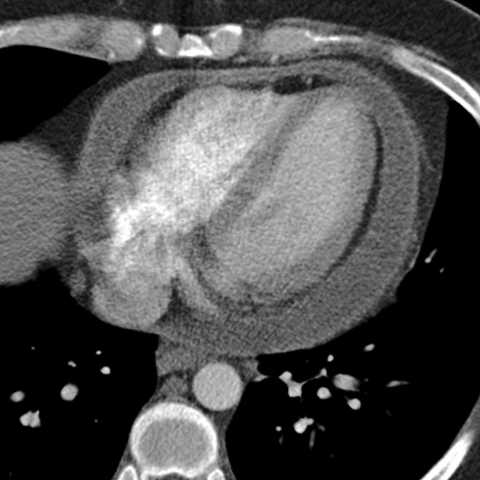

Pericardial Effusion [8 of 8]